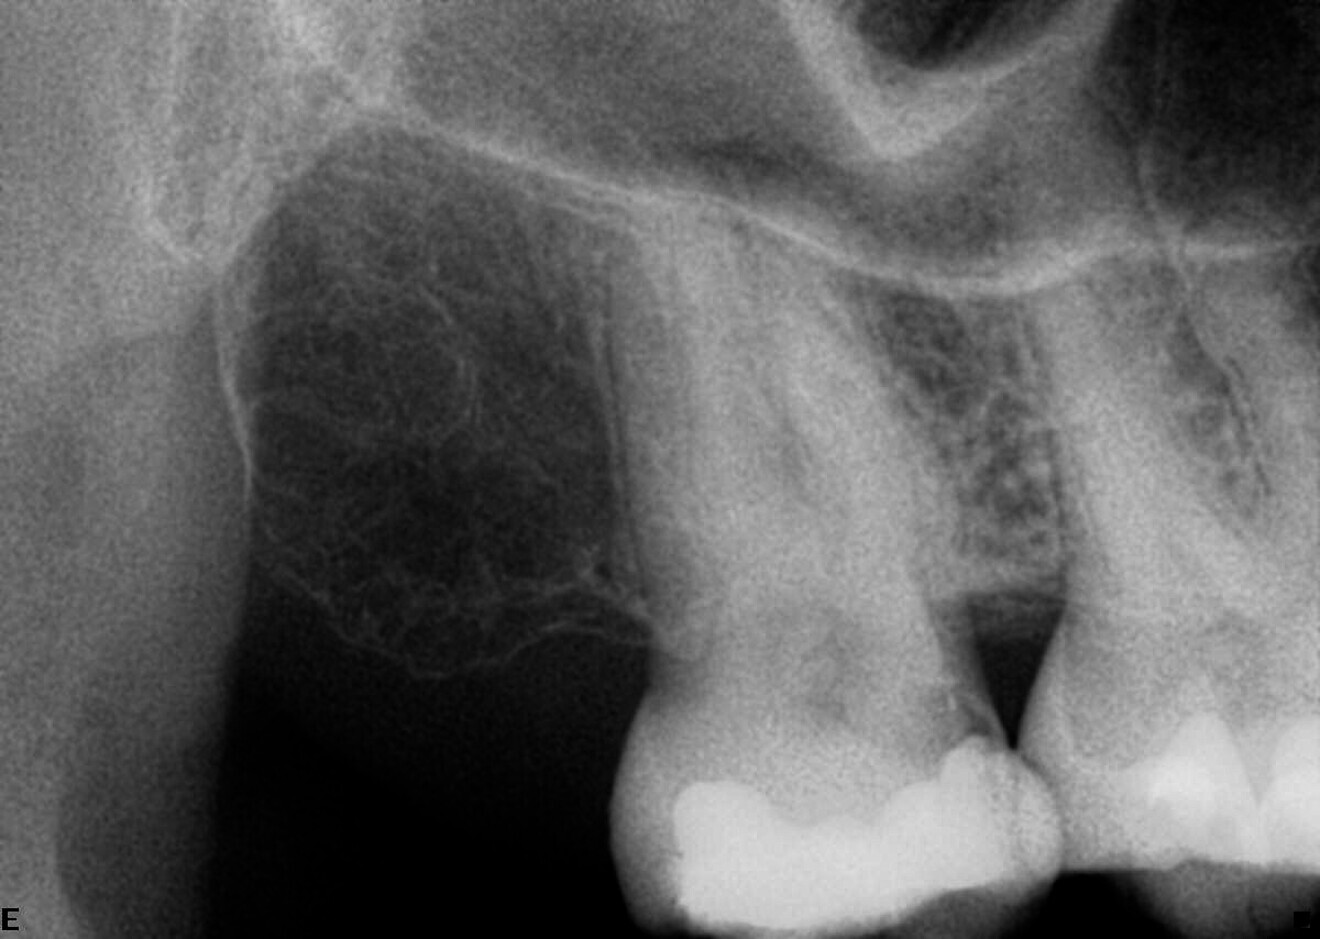

The patient was referred for treatment of irreversible pulpitis of a maxillary second molar. The preoperative radiograph revealed more roots than typically expected (Fig. 7). After accessing the cavity, a second palatal root was identified.

Shaping was performed using the Adaptive Motion sequence of ZenFlex CM files. When comparing the preoperative and postoperative radiographs, it is evident that the original anatomy was preserved and the curves were shaped in a conservative manner (Fig. 8).

Case 2—Fig. 7: Initial periapical radiograph.

Fig. 8: Postoperative periapical radiograph.